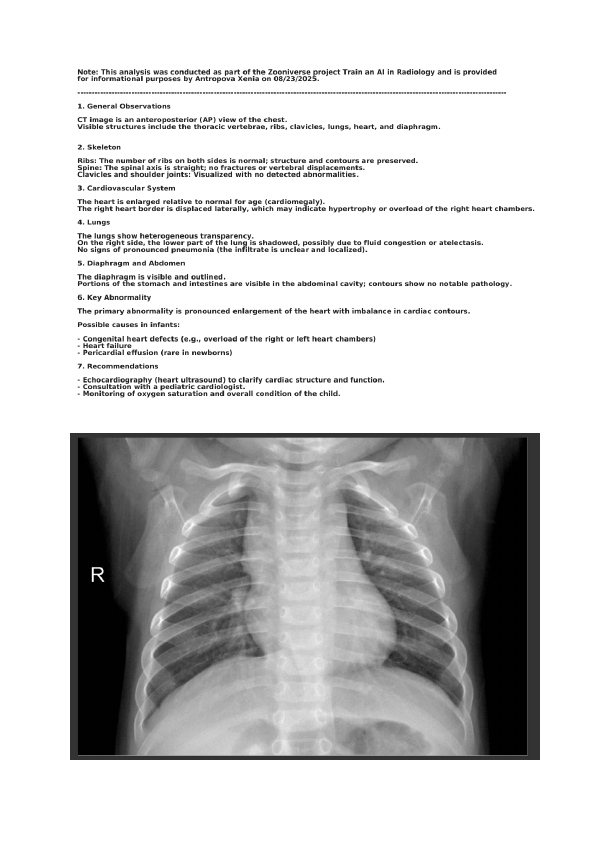

IT specialist dedicated to medical imaging, certified as a Medical Imaging Annotation Specialist (Micro1). Experienced in analyzing MRI scans (brain, spine, abdominal regions) and Chest X-rays. Skilled in identifying normal and abnormal structures to support AI research, dataset development, and medical projects. Contributor to Zooniverse projects "Train an AI in Radiology" and "Brain Match".

2. Zooniverse: 170 Chest X-ray cases (“Train an AI in Radiology”), 50 MRI brain scans (“Brain Match”)